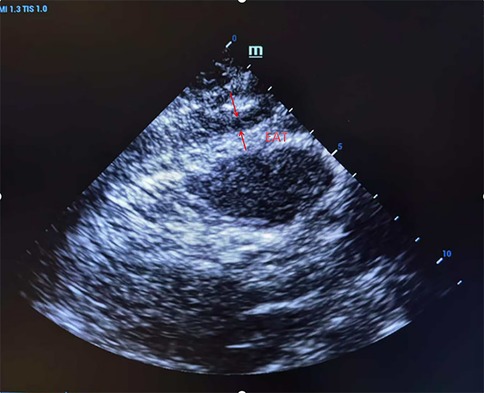

EAT measurement was assessed with Doppler ultrasonography (Shanghai Longyi Medical Devices Co., Ltd, model: XF3500). Measurement consisted of an initial low-frequency probe (2.5–3.5 MHz), followed by a high-frequency probe (7.5–10 MHz) for better resolution. In the parasternal long-axis view, we drew a line perpendicular to the right ventricular free wall level from the aortic annulus. At end-diastole, we measured fat thickness (EAT) between the free wall of the right ventricle and the visceral pericardium in five consecutive cardiac cycles, and we recorded the mean value (Figure 1).

Figure 1. Ultrasound detection of right ventricular anterior epicardial adipose tissue (EAT) thickness in parasternal long-axis view. A representative echocardiographic image showing a measurement of EAT thickness located between the right ventricular free wall and the visceral pericardium, taken at end-diastole.